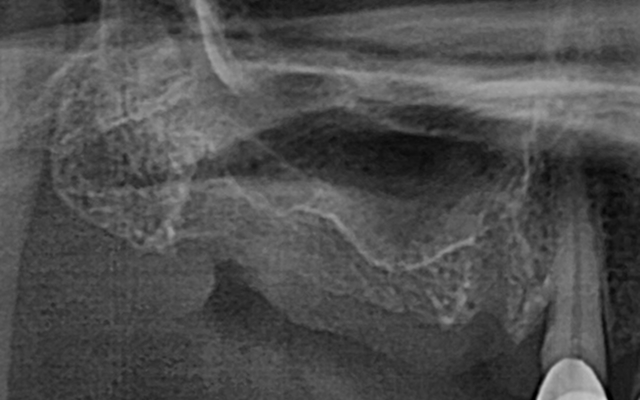

상악동 거상술 케이스

- 얇은 위턱 어금니 부위에 상악동을 거상하여 골량 보강

- 임상 경험을 바탕으로 합병증을 낮추고 예측 가능한 결과 도출